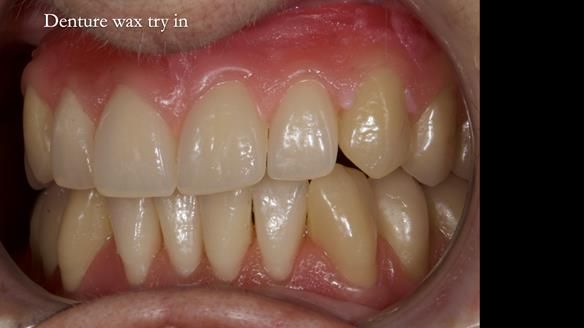

Welcome to Newsletter 83. This month I am sharing Sheila’s case — a very challenging but rewarding complete denture case. Sheila had flat ridges, a small mouth opening, a large tongue and had never been able to wear complete dentures of any kind. Everything was loose and sore. She felt embarrassed and looked older without dentures. She wanted a stable, comfortable result, and she wanted to avoid implants because she has taken bisphosphonates for more than five years.

In this newsletter I will take you through Sheila’s full protocol step by step — including impressions, French Impression Technique, Dr Abe shaping, copying Kirsty MacColl’s smile, the try-in, the final fit, and the copy dentures we made afterwards.